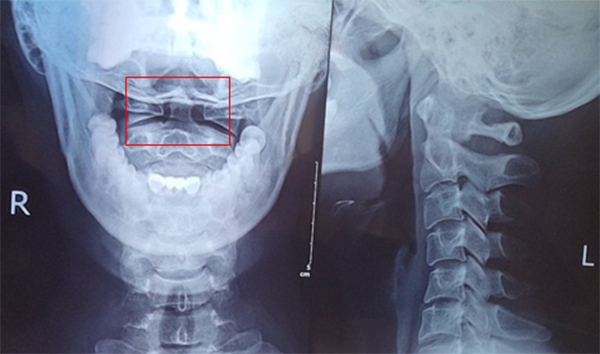

一張頸椎X線正側(cè)位片求得真因

(請注意是張口位,否則查不到病灶)

頸椎X線檢查結(jié)果:頸椎生理曲線變直、寰枕間隙略窄,鉤椎關(guān)節(jié)增生,右側(cè)寰齒間距窄,兩側(cè)寰齒間距差值大于2mm,左側(cè)寰椎側(cè)塊較右側(cè)略寬(見圖紅框中)。

X片結(jié)果,肯定了醫(yī)療團隊的分析思路,明確了臨床診斷:頸椎病,寰樞關(guān)節(jié)脫位。